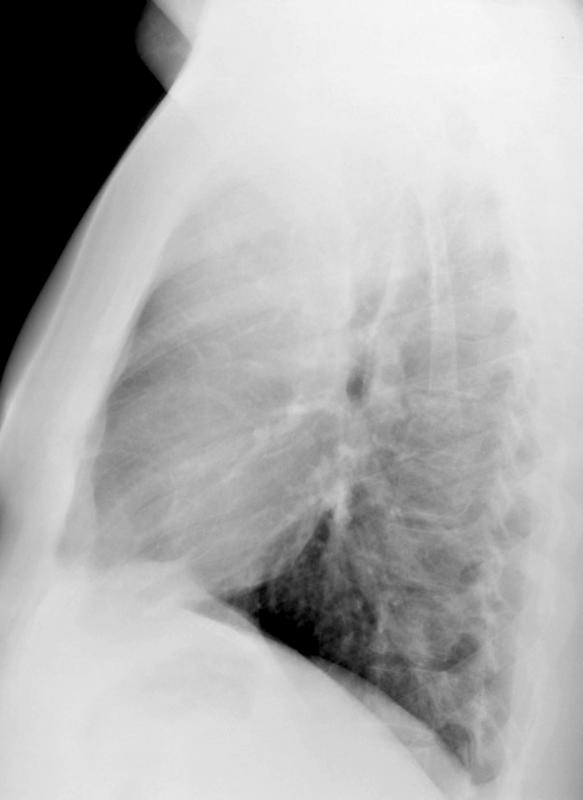

Gallery Mediastinum Lymphoma 5b

5b